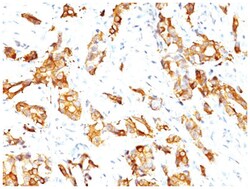

HSP27 Monoclonal specifically detects HSP27 in Human, Mouse, Rat, Chicken, Chimpanzee, Monkey, Sheep samples. It is validated for Western Blot, Flow Cytometry, Immunohistochemistry, Immunocytochemistry/Immunofluorescence, Immunohistochemistry-Paraffin.Specifications

| This MAb reacts specifically with heat shock protein HSP27 in human and monkey tissues and cell lines such as MCF-7. HSP27, also referred to as the Estrogen-Regulated 24K protein and HSP28, is one of several small heat shock proteins produced by all organisms studied. HSP27 synthesis is induced by elevated temperature, as well as by estrogen in hormone responsive cells. Interestingly, human HSP27 also shares greater than 50% homology with low molecular weight Drosophila HSPs and mammalian alpha-crystalline lens protein. Because of the estrogen responsive nature of HSP27, this protein has been studied extensively in human estrogen responsive tissues such as cervix, endometrium and breast tissue. Therefore HSP27 may be useful in classifying various hormone sensitive tumors. |